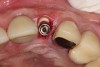

Appropriate rotary burs were used to section the tooth in half in the mesial-distal direction, followed by careful removal of the palatal root half (Figure 17). Next, the remaining labial root was contoured to a thickness of approximately 1.5 mm followed  by removal of the apical third (Figure 18). OD burs were then utilized to densify the bone in the osteotomy via lateral bone displacement (Figure 19). A bone grafting putty (Novabone) was placed into the osteotomy and the implant was then inserted with a primary implant stability reading of 60 Ncm (Figure 20). Typically, mineralized allograft is the preferred choice for grafting between the implant body and facial root.

After 2 weeks, excellent soft-tissue healing and maintenance of the labial gingival tissue was evident. The same was true after 3 months (Figure 21). The gingival zenith continued to be maintained after 1.5 years (Figure 22). Importantly, the facial wall bone thickness of the implant also was maintained at the 1.5-year follow-up (Figure 23), suggesting favorable maintenance of this case.

Fig 20. After placement of bone grafting putty in the defect, the implant was inserted. Note the remaining bone grafting putty on the buccal aspect of the implant.

Figure 20